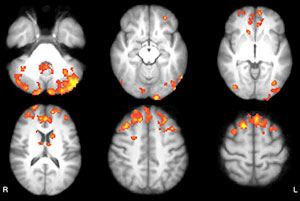

Axial functional connectivity (FC) maps show changes in thalamic FC after 8 weeks in both groups of patients with MS. Areas of increased FC are represented in red, areas of reduced FC in blue.

Figure 3: Axial functional connectivity (FC) maps show changes in thalamic FC after 8 weeks in both groups of patients with MS. Areas of increased FC are represented in red, areas of reduced FC in blue. A, Intervention group shows increased FC in occipital, medial, and lateral parietal and posterior cingulate cortices, bilaterally; decreased FC in vermis and left dorsal-lateral prefrontal cortex. B, Wait-list group shows increased FC in frontal, occipital, and medial parietal cortices, bilaterally; cerebellum; and right temporal lobe.